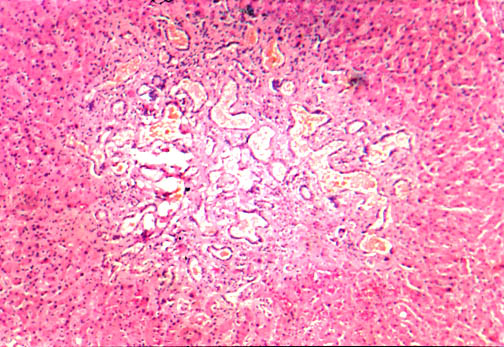

|   Fig. li-11-3-5. Congenital hepatic fibrosis. The parenchyma does not show any fibrous dissection nor regenerative nodules.